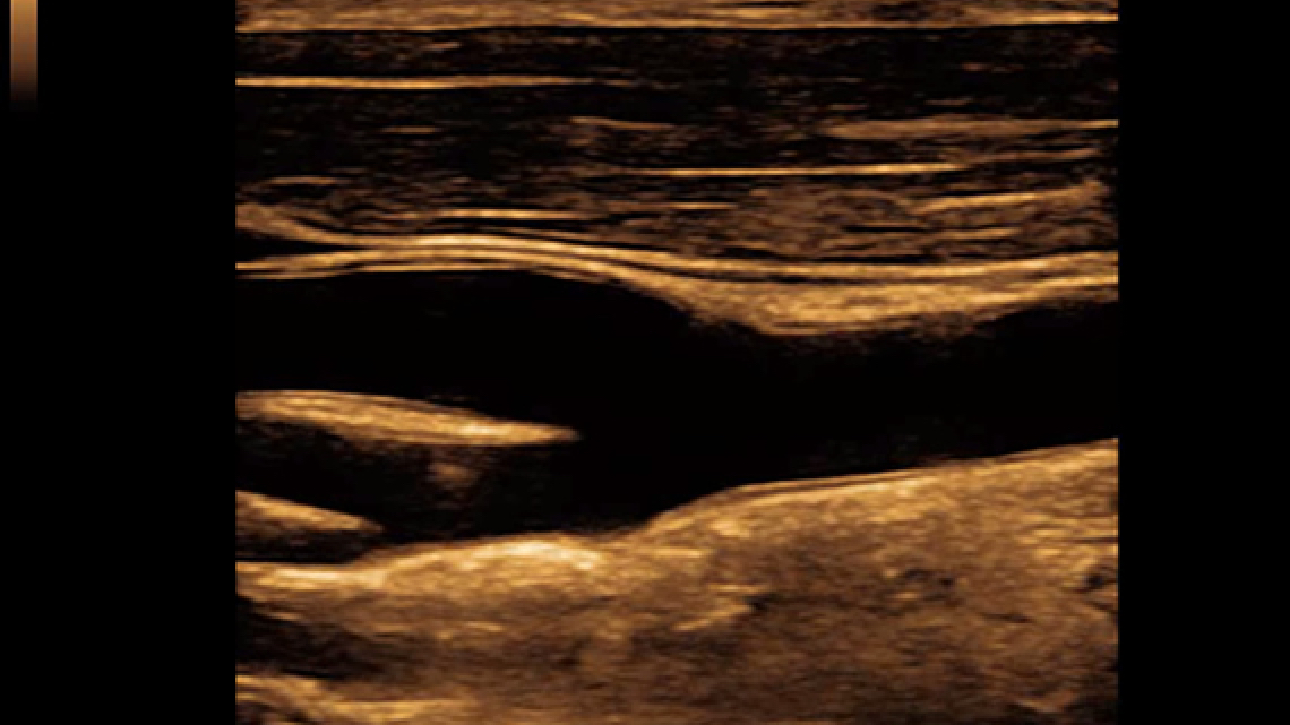

Smart Track

ItŌĆÖs Mindray unique feature to reduce repetitive, time-consuming scanning steps in vascular exams. Smart Track provides intelligent and real-time vessel tracking and real-time image optimization of Color and PW.